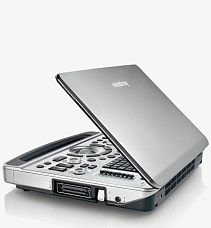

УЗИ аппарат Chison SonoTouch 80 Expert

Переносной ультразвуковой сканер Chison Sonotouch 80Exp является высокоточным диагностическим устройством. Он обеспечивает визуализацию на уровне стационарных систем экспертного класса, обладает умеренной ценой и богатым функционалом. Аппарат работает с высокоплотными датчиками, задействуется при проведении 3D/4D-УЗИ и эластографии. Эргономичная панель управления позволяет добраться практически до любой функции за одно нажатие и имеет функцию автоподстройки подсветки в зависимости от окружающего освещения. Портативный УЗИ аппарат Sonotouch 80Exp оснащен бесштырьковым портом для подключения легковесных ультразвуковых датчиков одним движением.

Вы можете заказать или купить со склада в наличии УЗИ аппарат Chison Sonotouch 80Exp по выгодной цене, от надежного официального дистрибьютора "Медицинские системы и технологии", с доставкой в любой город по всей России.